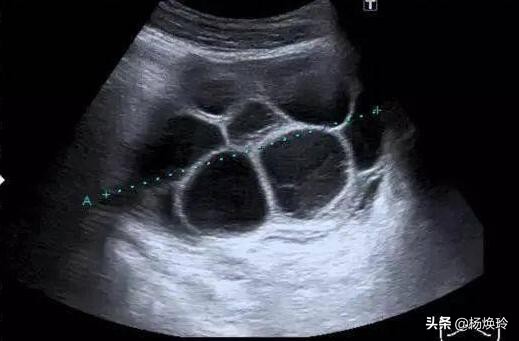

事后,我为她讲解卵巢过度刺激综合 征,这种病为体外受孕辅助生育的主要并发症之一,是一种人体对促排卵药物产生的过度反应,以双侧卵巢多个卵泡发育、卵巢增大、毛细血管通透性异常、异常体液和蛋白外渗进入人体第三间隙为特征而引起的一系列临床症状的并发症。会 引起患者胸腹水,尿少,血液浓缩,电解质紊乱,肝肾功能受损的变化,威胁患者生命。小刘苦恼不已,难道就不能要孩子了?